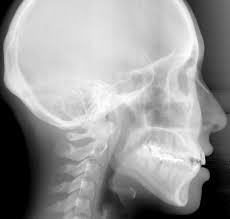

cephalometric x-ray

Kita tidak boleh menganggap remeh penggunaan sinar X di bidang kedokteran maupun kedokteran gigi. Menurut sebuah penelitian baru, bahkan dosis rendah radiasi dari sinar X dapat memicu penyakit jantung maupun stroke.

Tim menemukan bahwa radiasi sinar X dapat membunuh monosit (salah satu jenis sel darah putih) yang terdapat pada dinding arteri. Hal ini ternyata dapat mengakibatkan meningkatnya kadar monocyte chemo-attractant protein 1 (MCP-1) yang dapat mengarah kepada penyakit kardiovaskular.

Penulis mengatakan resiko yang didapat dari paparan radiasi sinar X tingkat rendah, seperti yang terdapat pada bidang kedokteran maupun kedokteran gigi, mungkin lebih besar dari yang sudah kita perkirakan sampai sekarang.